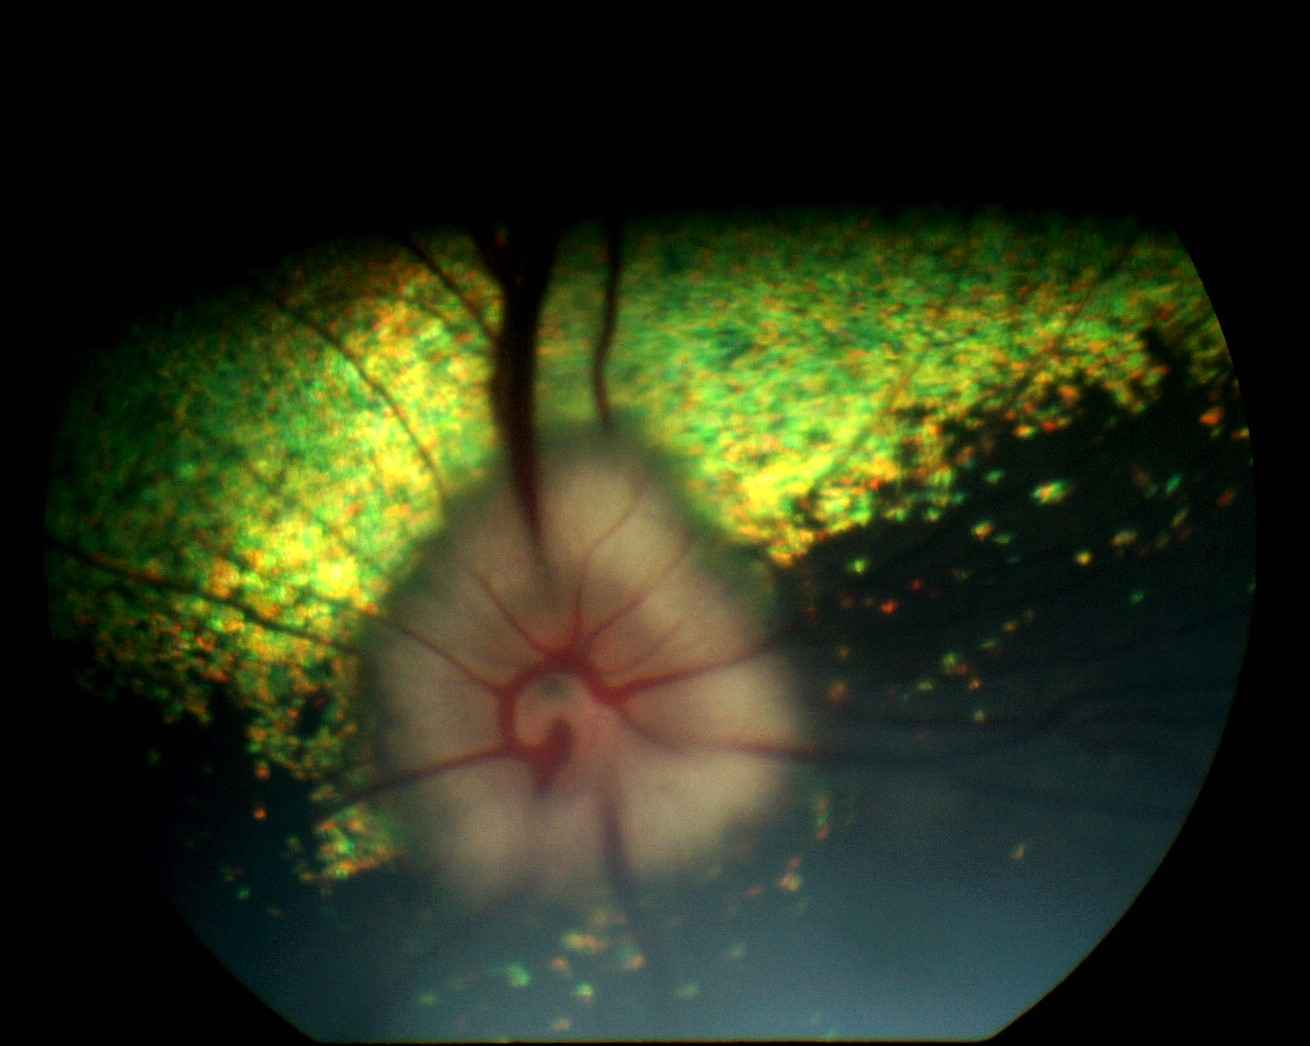

Photo n° 1A : OEil droit : aspect mamelonné et reflet de la zone sans tapis bien visibles.

Les aires pupillaires apparaissent totalement occupées par un voile grisâtre translucide, d'aspect mamelonné, au sein duquel des vaisseaux sanguins aux contours nets sont remarqués. Les cristallins sont en place et transparents. Les zones du tapis (jaune orangé) et sans tapis (sombre) du fond d'oeil sont identifiables mais floues à droite et à gauche (photos n° 1A et 1B).

La neurorétine, translucide, est totalement décollée à droite et à gauche, sans qu'aucune partie de tapis choroïdien ou de zone sans tapis ne soit directement visible, ce qui est en faveur d'une absence de déchirure (trou rétinien).

Selon les propriétaires, le chien évolue normalement dans son milieu habituel au bout de 5 jours de traitement et les consultations de contrôle à 2 semaines, 1 mois et 6 mois témoignent d'une réapplication rétinienne et d'une vision restaurée avec un fond d'oeil normal à droite et à gauche (photos n° A à F). G.C.